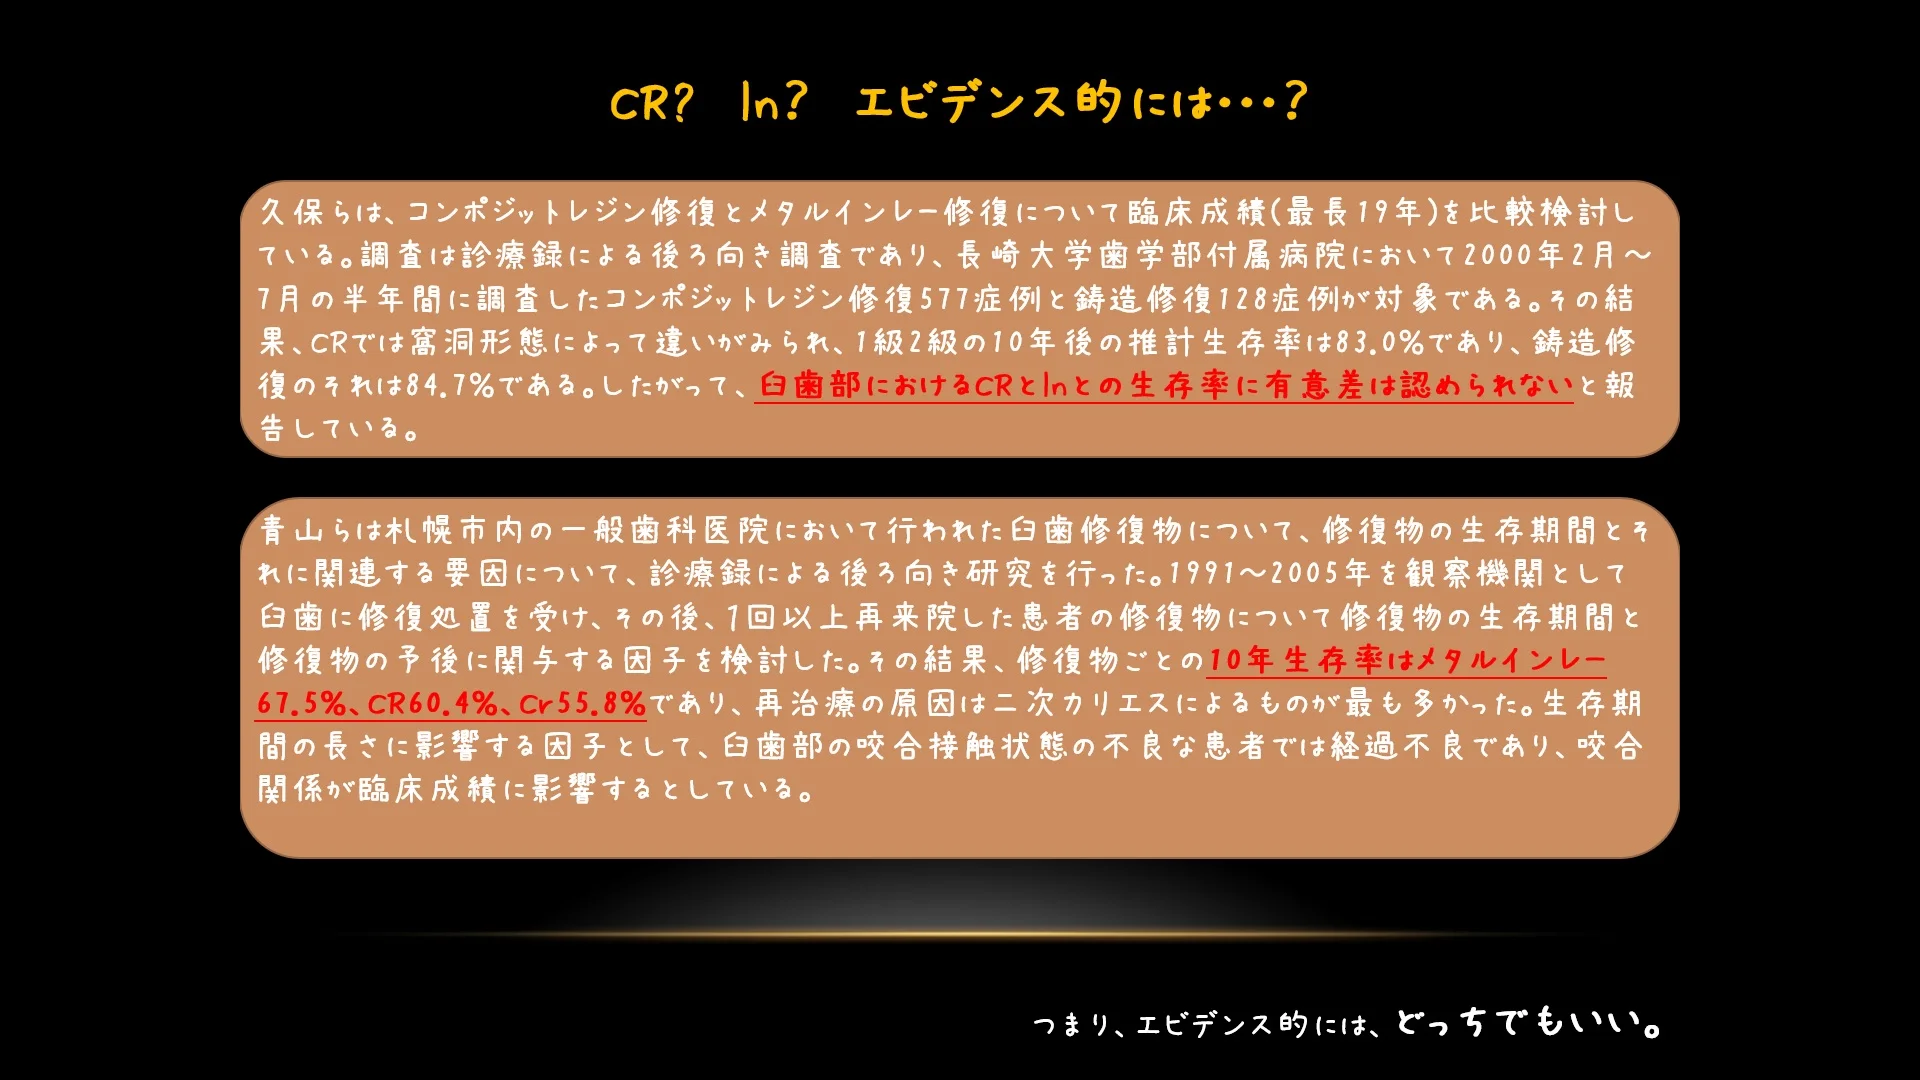

Q&A~白い詰め物と金属の詰め物どちらがいい?~

こんにちは。 最近涼しくなってきましたね! 私は暑がりなので、非常に幸せです・・・。 これからは過ごしやすくなりそうで嬉しい限りですが、涼しくなっても熱中症って起こりますから引き続き注意してくださいね。 さて。 今回は、8月に機会があり講演…

【歯科医師向け】アジア人の奥歯むし歯治療でどの素材が長持ちしやすいか?|臼歯部修復の材料選択と長期予後の考え方

奥歯のむし歯治療で「どの素材が一番長持ちしますか?」と聞かれることは少なくありません。このコラムでは、ジルコニアインレー・e.maxインレー・CAD/CAMハイブリッドレジンインレー・直接コンポジットレジン修復について、アジア人を含む臨床研…